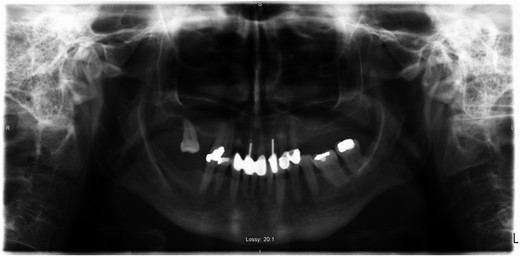

A 69-year-old female with a history of bilateral total hip replacements presented with rigors, fever and sudden onset left groin pain. A pelvic X-ray showed well-fixed implants. Blood results revealed a leucocytosis (white cell count 22.3 × 109 l–1) and elevated C-reactive protein (211 mg/l). Ultrasound-guided aspiration of her left hip grew Streptococcus gordonii. No source infection could be identified apart from a new chronic sinus infection in a left upper incisor. Following a discussion with the patient a 6-week course of intravenous ceftriaxone was started and was successful in normalizing her inflammatory markers. She was placed on long-term suppressive amoxicillin following this. Her suppressive antibiotic therapy was complicated by the development of a clostridium difficile infection and her antibiotics were changed to doxycycline. At 1-year follow-up, she was asymptomatic with no further episodes of groin pain or fever.

PJI occurs via direct inoculation, contiguous or haematogenous spread. Late onset infections (>12 months after surgery) are predominantly due to haematogenous seeding of virulent pathogens at another site (urinary tract, soft tissue infection). PJI is primarily caused by staphylococci with only a small percentage caused by streptococci, <10% [1, 2]. Streptococcus gordonii, a member of the Streptococcus Sanguinis group, a subdivision of VGS, is one of the microbiota of the oral cavity that contributes to plaque formation. It is recognized in the setting of bacterial endocarditis [3], but has only recently been described in the literature as causing PJI, in the setting of total knee replacement reported in 2015 [4].

- incisors

- sinusitis